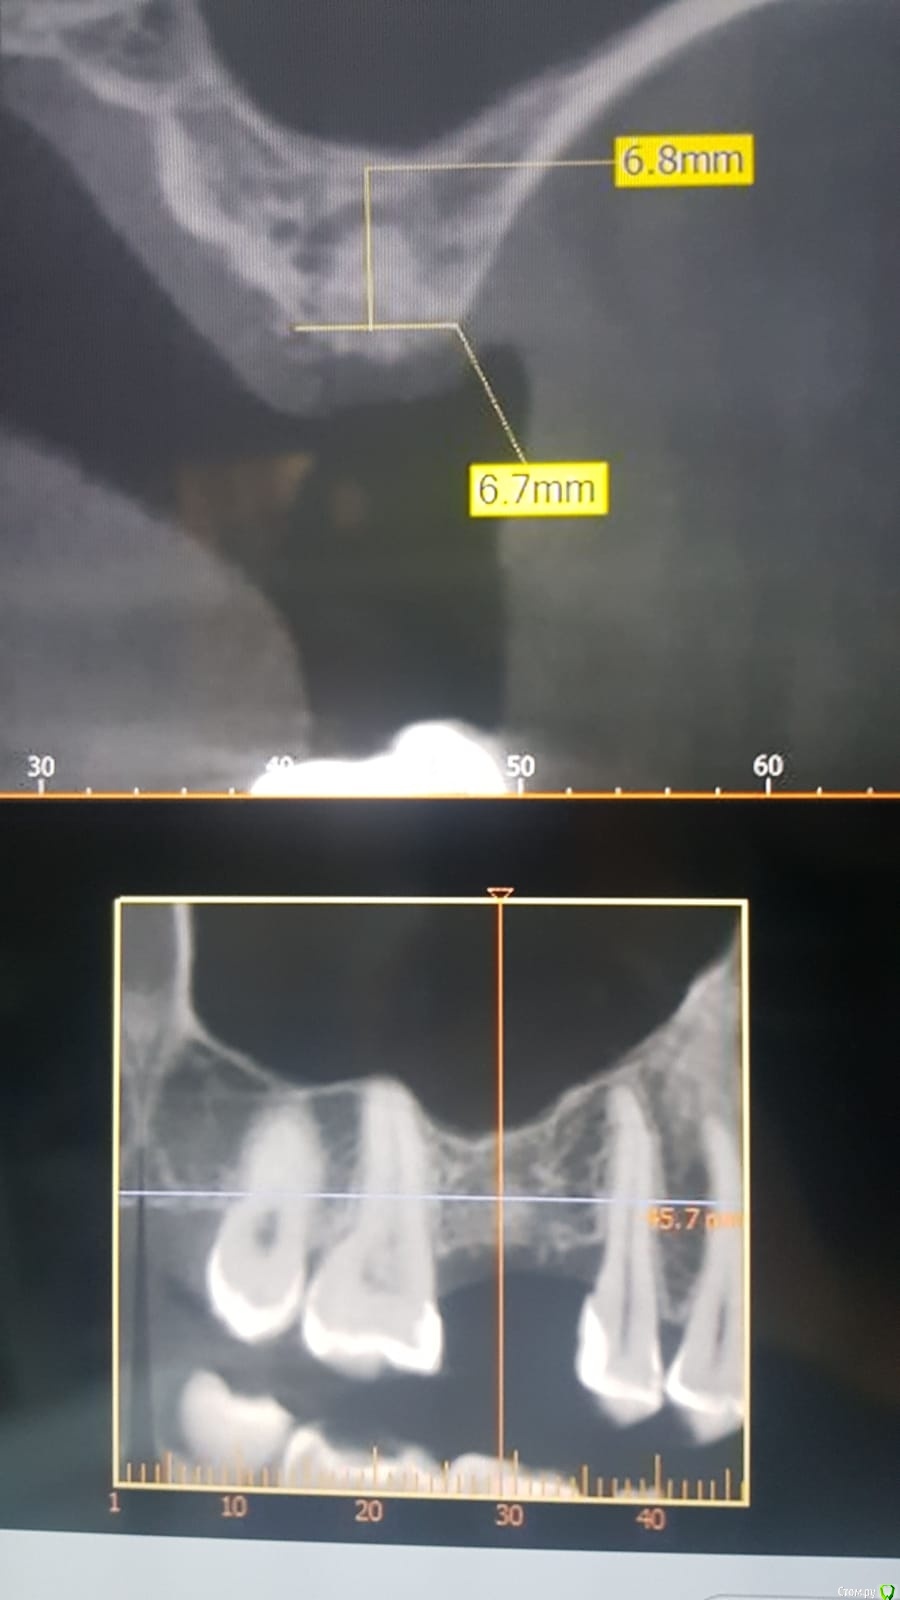

elizaveta73 Опубликовано 22 января, 2021 Поделиться Опубликовано 22 января, 2021 Здравствуйте!Прошу вас высказать свое мнение относительно возможности имплантации. Толщина кости верхней челюсти всего 6,8 мм. Возможна ли имплатация в данном случае или необходим синус лифтинг? И, если имплантация возможна, абатмент какой фирмы будет оптимальным? Ссылка на комментарий

dok1 Опубликовано 22 января, 2021 Поделиться Опубликовано 22 января, 2021 3,9х8 и чуть подстучать. Необходимый минимум. А уж если формик и мяска подкинуть - вообще огонь будет 1 Ссылка на комментарий

Борис80 Опубликовано 25 января, 2021 Поделиться Опубликовано 25 января, 2021 можно обойтись без синуслифтинга если совсем просто 2 Ссылка на комментарий